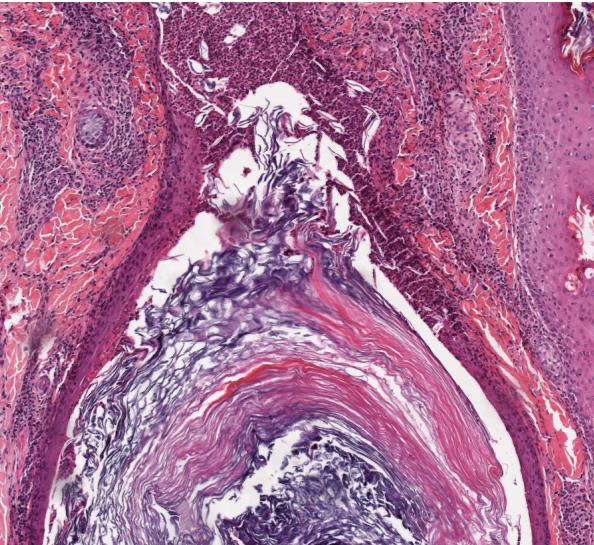

Identify. What condition is this seen?

Hamburger sign: vertically oriented split in the hair shaft containing proteinaceous material and erythrocytes TRICHOTILLOMANIA